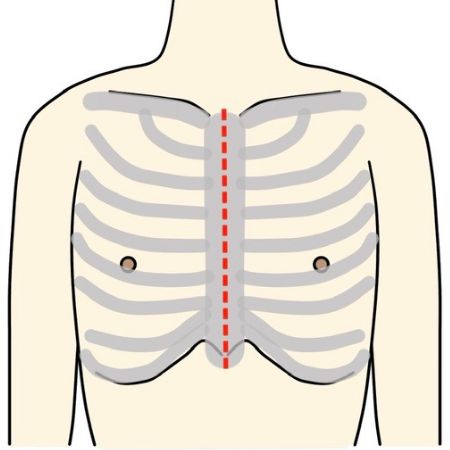

“体に対する負担が少ない手術”です

Minimally Invasive Cardiac Surgeryの略で、心臓低侵襲手術のことを意味します。

従来であれば胸骨という胸の真ん中を約20cm程切開しますが、MICSでは肋骨の間を3〜5cm程切開して行います。